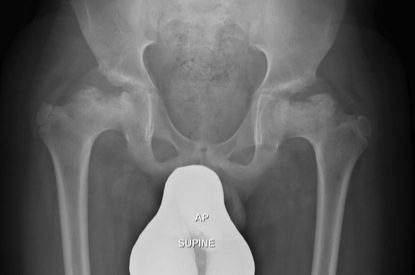

Hip

Most frequently & severely involved

- Coxa vara

- small irregular & fragmented capital epiphyses

- progressive flattening & extrusion of head

- poor head coverage

Premature OA common